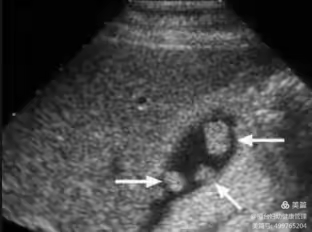

胆囊息肉在常规超声上多表现为胆囊壁上的高回声,后方无声影,不随体位改变而移动